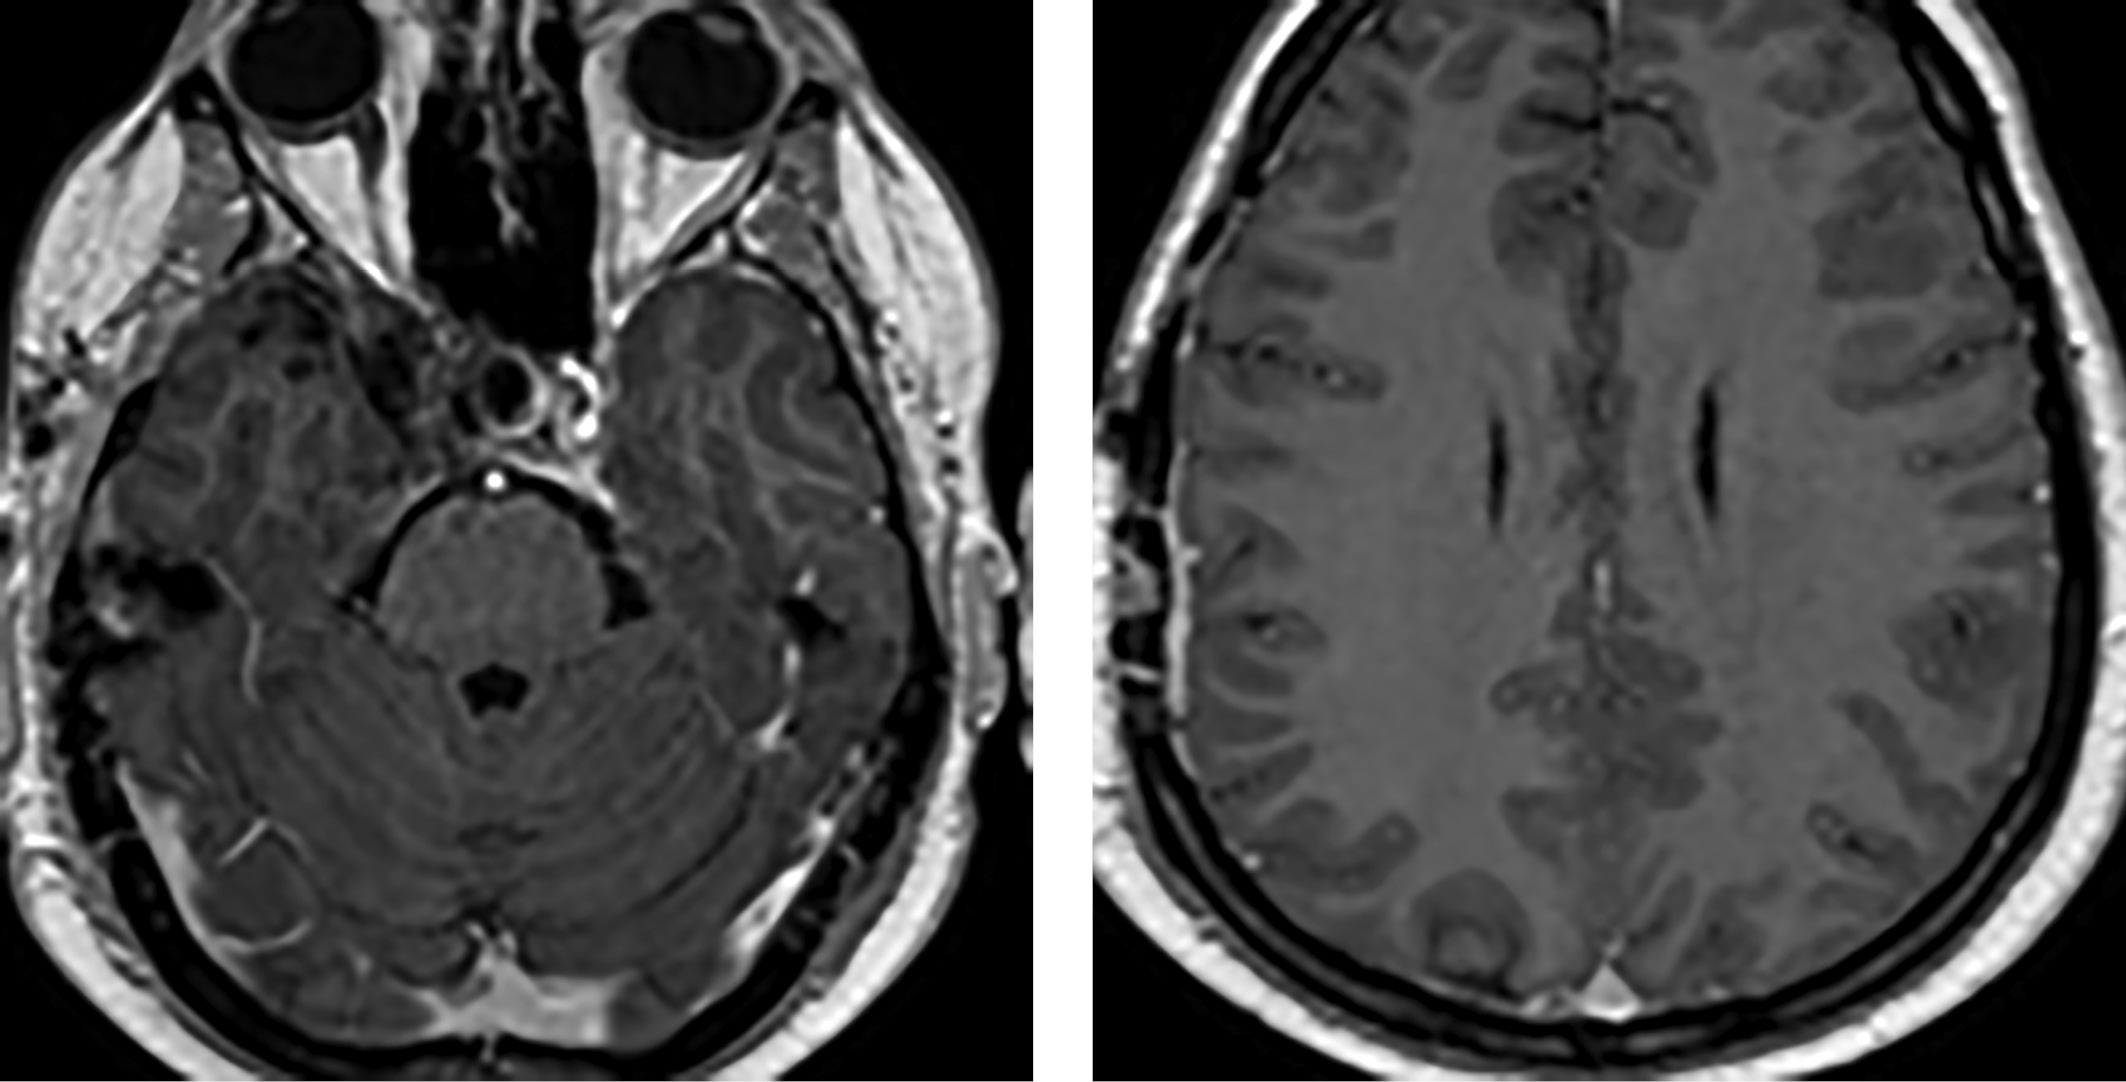

В 2015 г. в связи с появлением жалоб на головные боли было проведено МРТ-исследование головного мозга, выявившее объемные образования правой височной области и области задней поверхности пирамиды височной кости, убедительных данных за продолженный рост опухоли в области правого кавернозного синуса нет (рис. 1).

Рисунок 1. МРТ головного мозга пациента С. 35 лет визуализируются опухоли правой височной области и области задней поверхности пирамиды височной кости.